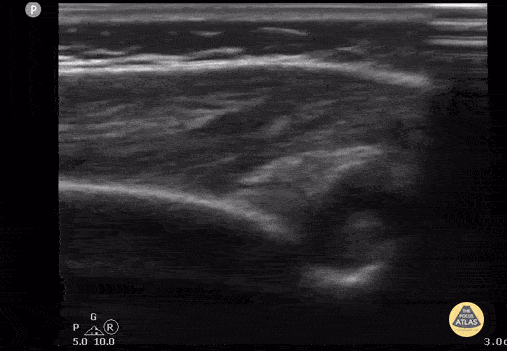

8 month old with arm swelling and fever. Longitudinal view of elbow with fluid collection displacing the posterior fat pad. Final diagnosis was septic arthritis of the elbow. Contributor: Antonio Riera, MD, Yale University School of Medicine